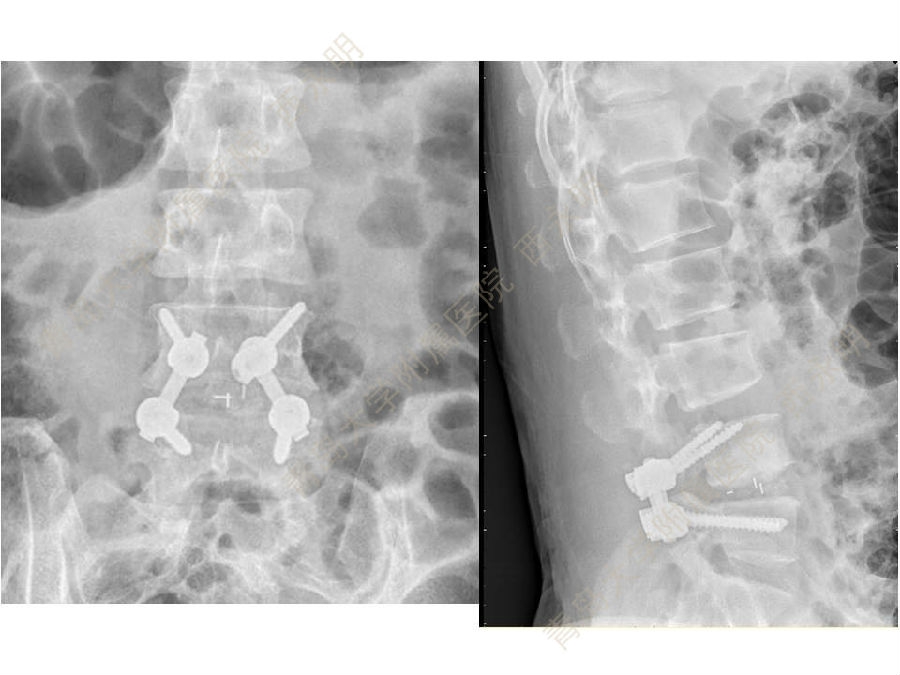

皮质骨螺钉技术及临床应用

颈椎伤病、脊柱畸形和脊柱肿瘤以及颈胸腰椎退变性疾病的微创治疗。长期从事临床一线的医、教、研工作,在多年的临床实践中积累了丰富的经验,并形成了以脊柱外科为专业方向,以颈椎外科、脊柱畸形和脊柱肿瘤为专业特色。